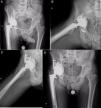

A) Radiografía anteroposterior de un paciente intervenido en otro centro; se aprecia aflojamiento y migración del anillo acetabular. B) Radiografía postoperatoria tras revisión con cotilo de metal trabecular con suplemento superior, Cup Cage e injerto óseo. Se puede observar un correcto relleno del fondo acetabular y la correcta colocación del implante.